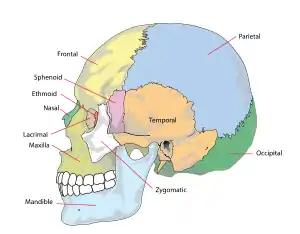

Crâne d'être humain : l'os occipital est en vert.